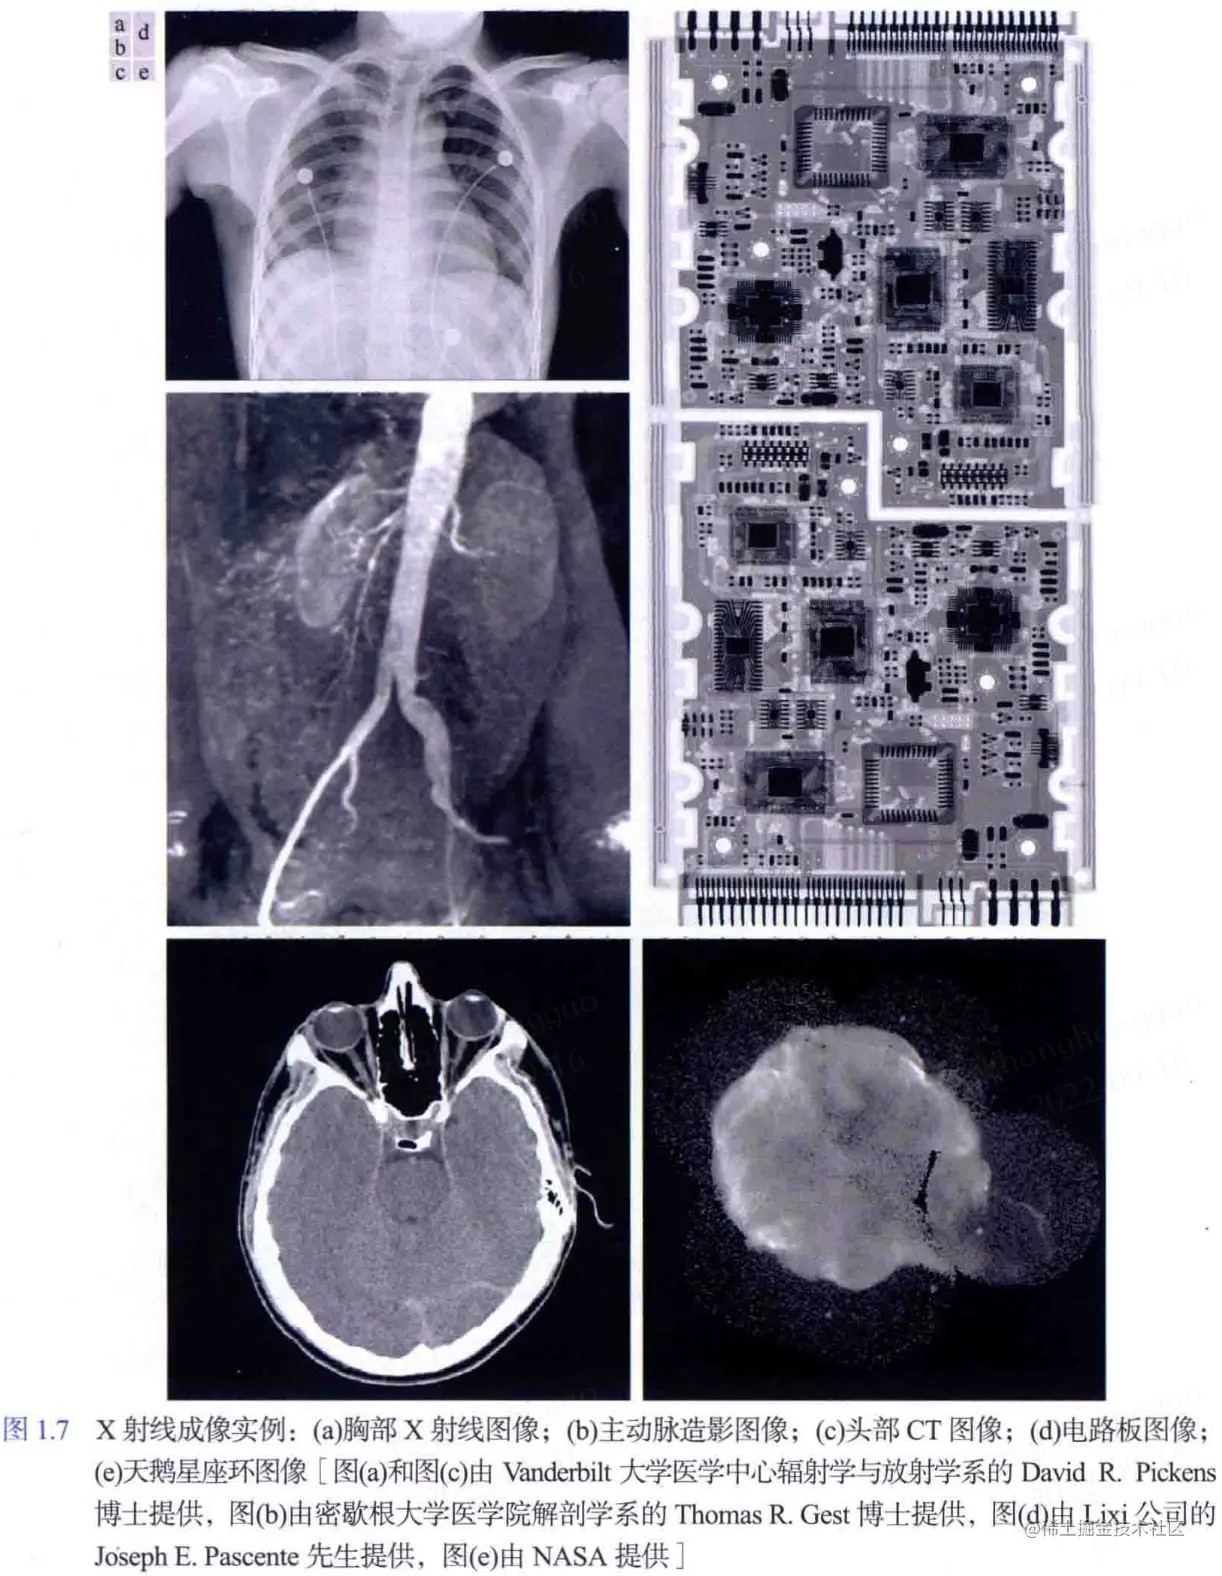

2. X 射线成像:X 射线成像除了应用于医学诊断,还被广泛应用于工业和其他领域,如天文学。

一些图像实例效果图如下图所示。

X射线成像实例